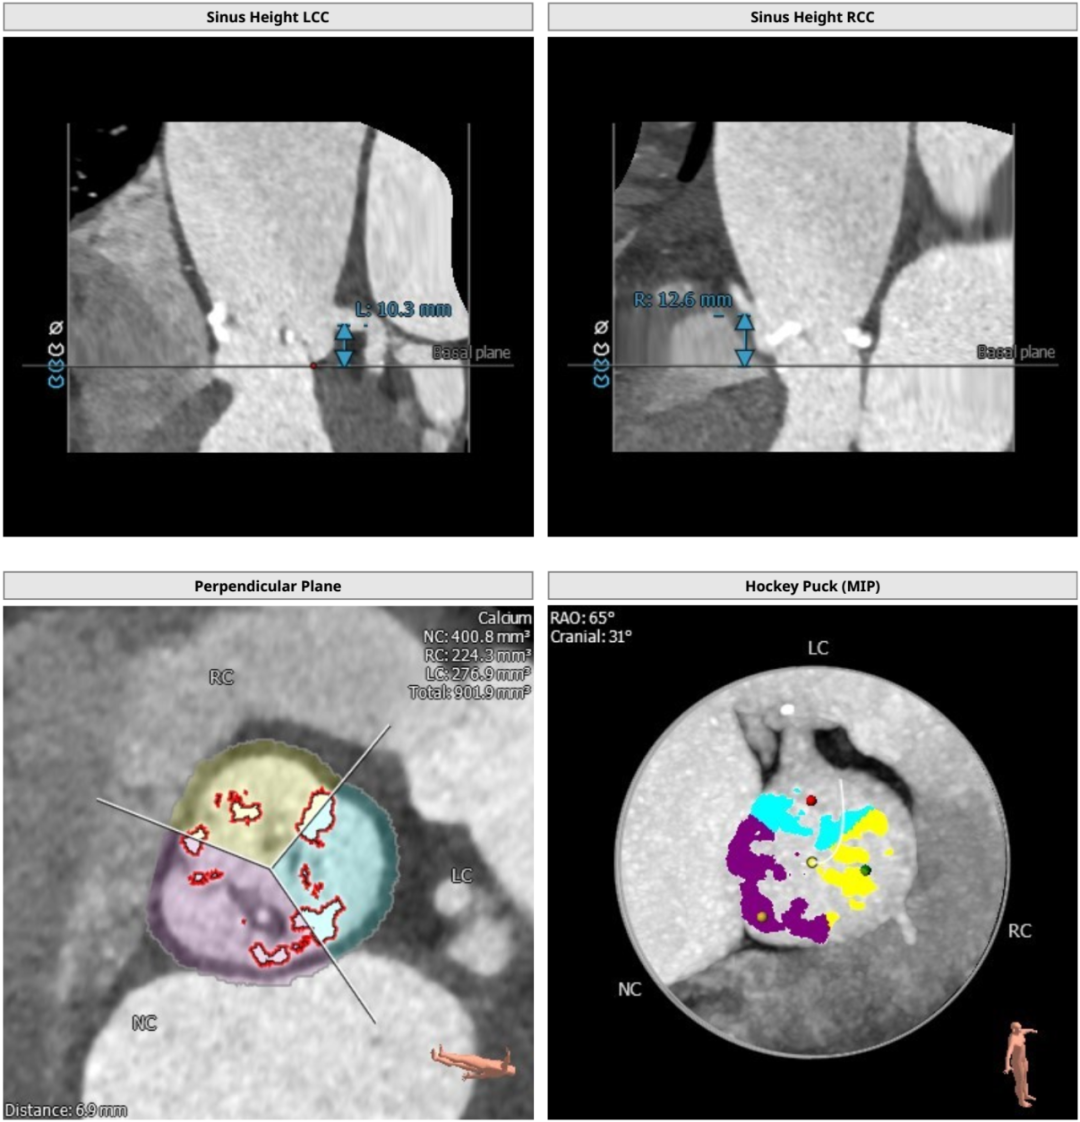

根部解刨: